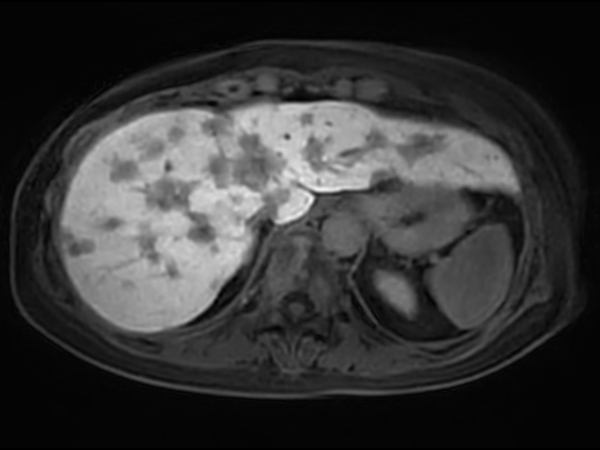

Axial T2w SSh